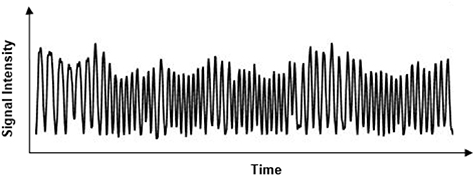

XD-GRASP is a novel method for dynamic image reconstruction based on a continuous scan during free breathing developed by Feng et al (2016). It is based on reconstructing the extra respiratory motion dimension from the acquired k-space data (figure 2). In the context of 3D liver imaging, this reconstruction is performed by solving the following optimization equation using compressed sensing:

Figure 2. Respiratory signal extracted from k-space data center.

Standard image High-resolution imageF is the Non-Uniform Fast Fourier Transform (NUFFT) operator defined on the radial sampling pattern of each frame of x, where x is the 3D dynamic image-series and y is the corresponding multicoil radial k-space data sorted into several contrast phases. Furthermore, S represents the coil sensitivity maps estimated using Walsh method (Grimm 2015) from the multicoil reference image given by the coil-by-coil NUFFT (Fessler 2019) reconstruction of k-space data by averaging all the acquired spokes. Here, C1 and C2 are the sparsifying transforms with weighting parameters  and

and applied in the contrast-enhancement dimension and along the extra respiratory state dimension, respectively. The same sparsifying transform 'Total Variation' constraint was used for both the respiratory dimension and the contrast enhanced phase but with different weighting parameters. The sparsifying transform is based on removing unwanted details while preserving important details such as edges, while the duration of each contrast-enhancement phase was 6 s. This transform plays an important role in removing streaking artifacts or the interspokes k-space information in frequency domain (Block et al 2007). The total number of spokes acquired was 691.